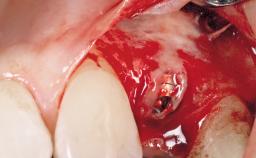

Immediate Flapless Placement of an Implant in a Maxillary Right Lateral Incisor Site

This 43-year-old male patient, a non-smoker, came to our practice because of a fracture of tooth 12 caused by a bicycle accident. Due to the combined para- and infrabony crown and root fracture, tooth extraction, and subsequent implant placement were suggested to the patient as the therapy of choice. The patient had high esthetic expectations with regard to the treatment outcome and asked for an immediate fixed provisional restoration. His individual esthetic risk profile summed up to a medium esthetic risk.

Placement Protocol Immediate implant placement

Socket Morphology Single-root socket

Socket Integrity Sufficient, with intact bone walls

Bone Volume Sufficient, with intact walls